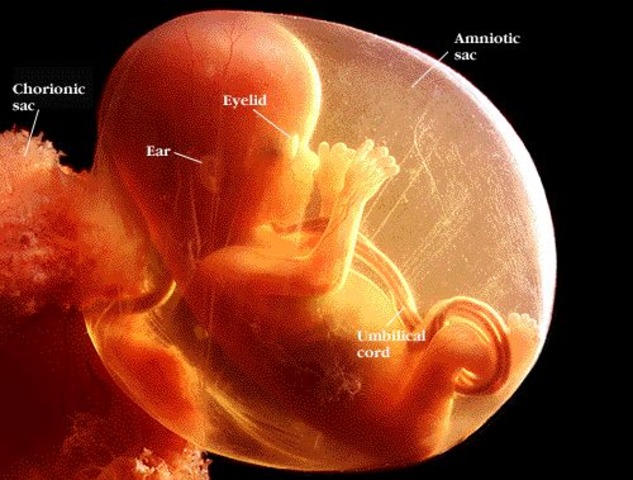

• Week 8

Week 8

The tiny person is protected by the amnionic sac, filled with fluid. Inside, the child moves gracefully.